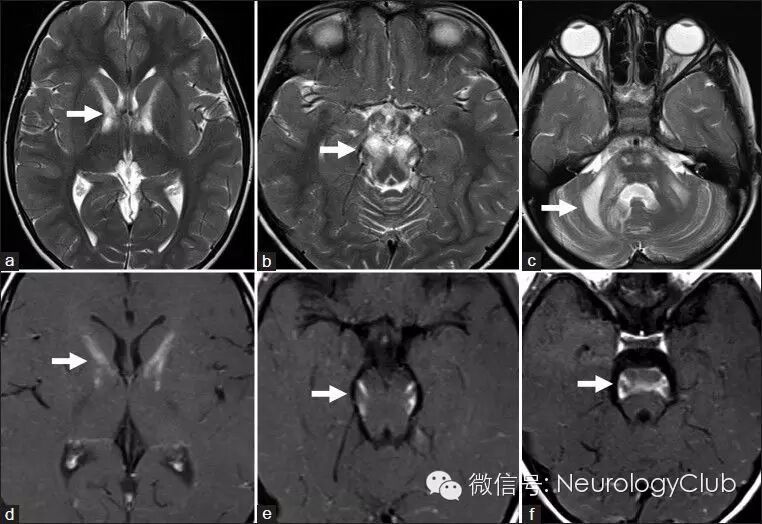

(a-c:T2WI;d-f:T1+C)